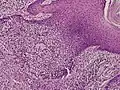

Microscopic histopathological examinations of the tumor tissues of all poroma variants stained with hematoxylin and eosin dyes reveal: a) basophilic "poroid cells" (i.e. small, cuboid-shaped cells with oval nuclei which resemble cells in the peripheral layer of the distal portion of eccrine sweat gland ducts[20]) that may form cords and broad columns extending downward from the epidermis; b) larger cuticular cells (i.e. squamous epithelial-like eosinophilic cells that resemble the luminal cells lining eccrine sweat gland ducts[20]); and in some cases c) clear cells (i.e. cells with small nuclei surrounded by pale cytoplasm).[3] Poroma tumor tissues may appear highly vascularized and/or have areas of necrosis, i.e. dead or dying cells. Hidroacanthoma simplex variants are mainly composed of poroid cells, few cuticular cells, and no clear cells and are confined to the epidermis; dermal ductal variants are mostly confined to the superficial dermis and are composed of small solid and cystic nodular aggregates of poroid, cuticular, and clear cells; poroid hidradenoma variants have large aggregates of solid and cystic components and extend deeper into the dermis or even subcutis; and eccrine poroma variants are composed of all three cell types but are primarily located in the epidermis and superficial dermis. Poromas may have 2 or more of these variants in the same tumor tissue and the variants typically have histopathology findings that are not clearly distinguishable from each other.[3]